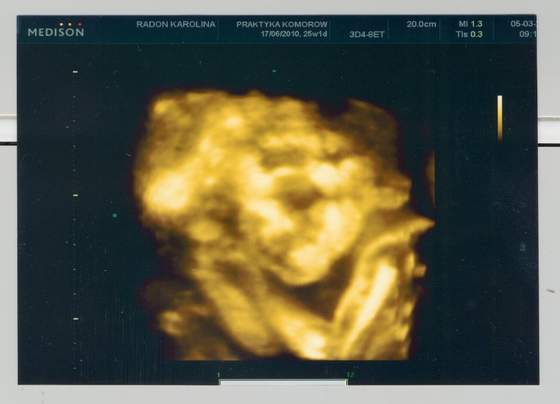

Nasze fasolki na USG

A to jest Hania :-)

2gtneoz..jpgx1lhl2..jpg

cudowne maluszki, dziewczyny ! ależ one nam szybko rosną :D nasz synek w ubiegłym miesiącu miał 330g a teraz już 640g ! rosną jak na drożdżach :D